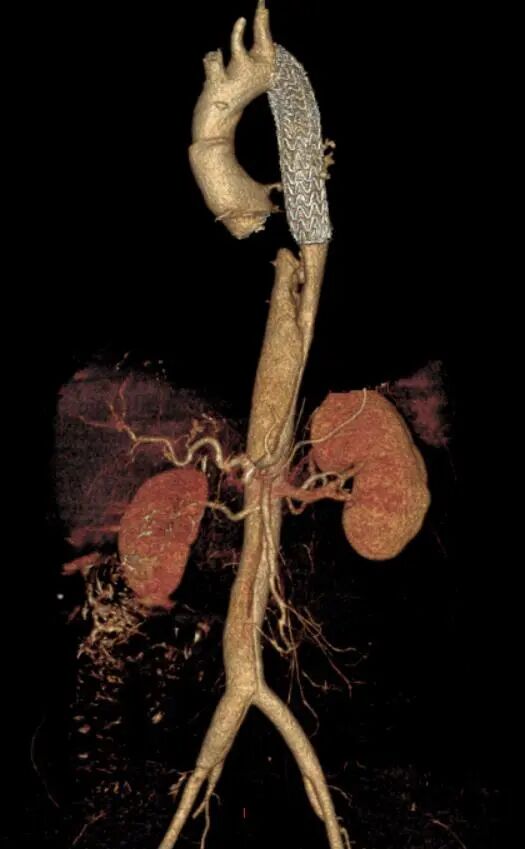

患者完成Bentall手术后进行CTA复查,CTA显示近端假腔隔绝,支架位置形态良好。

术后3D重建

gore医疗怎么样「胸有乾坤」可调可控 分毫必争—GORE®TAG® 可主动调控胸主动脉覆膜支架治疗B型主动脉夹层伴升主动脉瘤病例报道_https://www.jmylbn.com_新闻资讯_第17张

矢状位动态